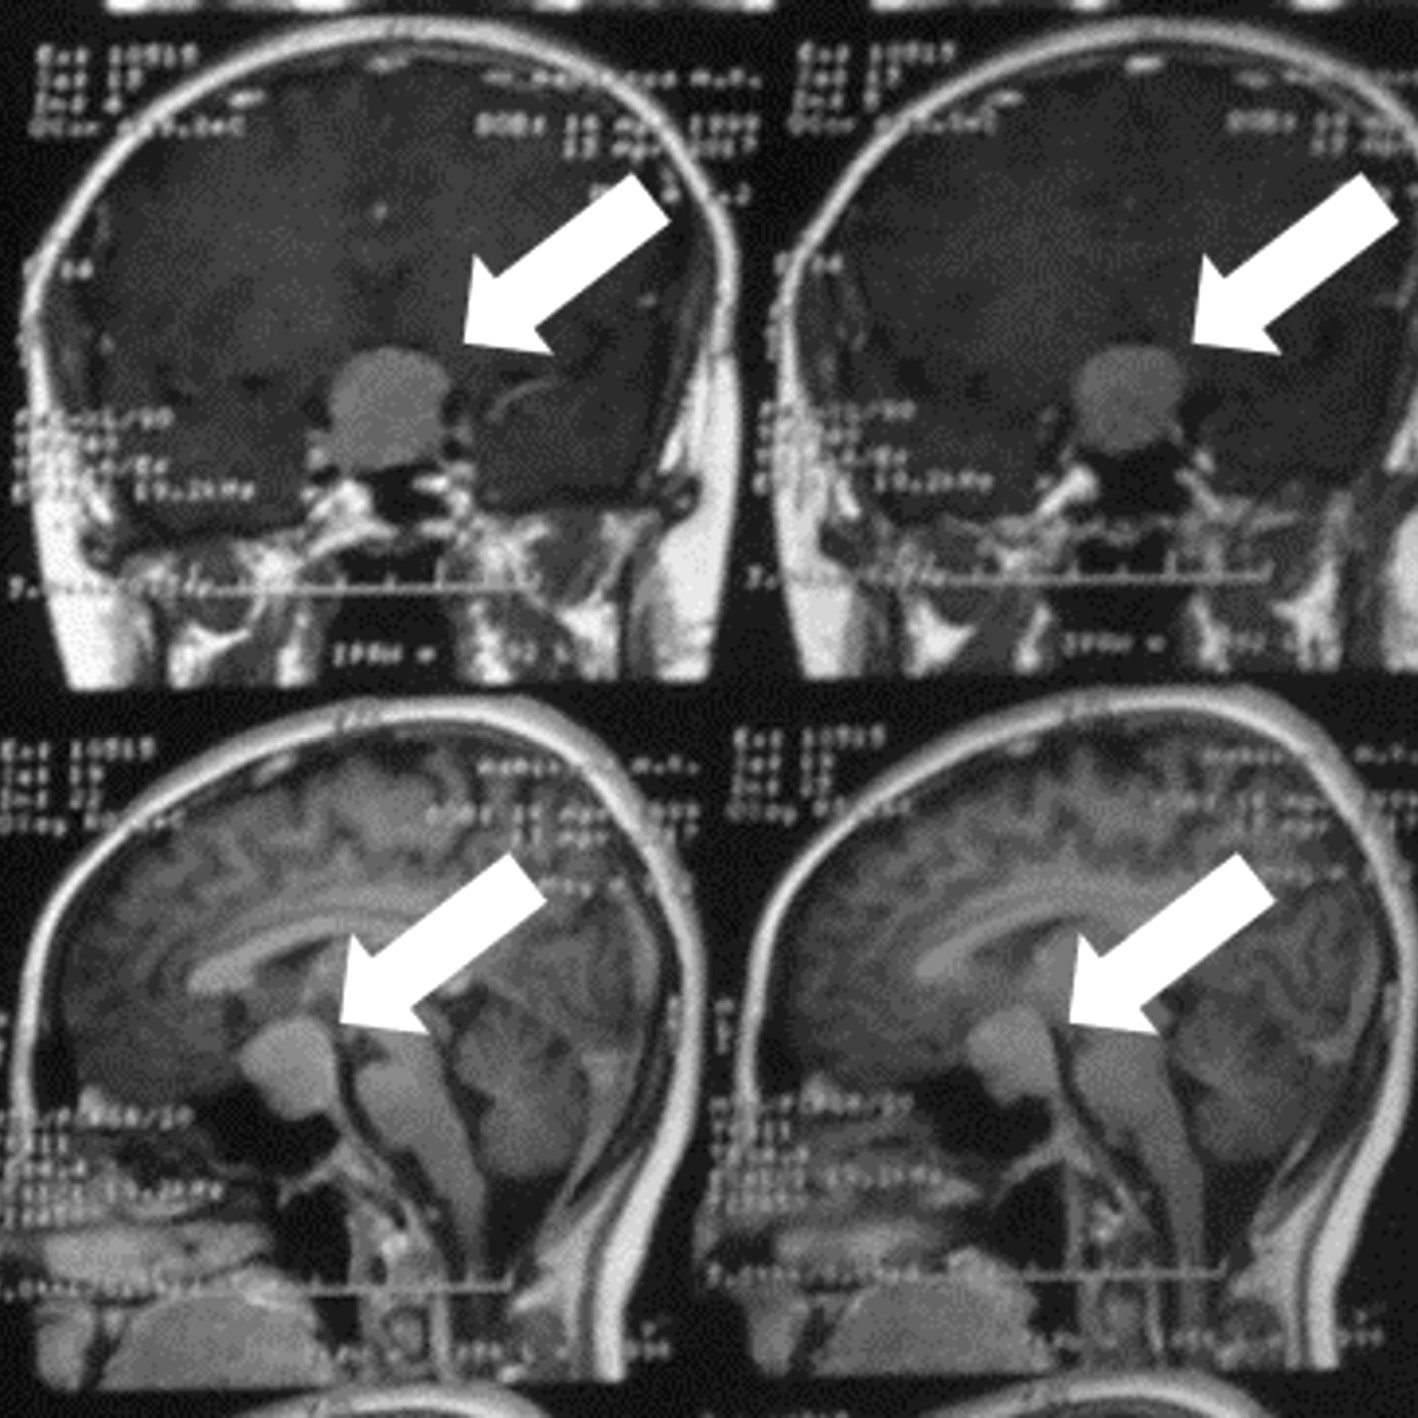

При сборе анамнеза установлено, что вышеописанные жалобы беспокоили с 2016 г. Менструальный цикл регулярный. В дебюте заболевания пациентка обратилась к гинекологу по месту жительства, при осмотре и по данным УЗИ выявлены двусторонние множественные кисты яичников. Пациентка была направлена в ФГБУ «НМИЦ АГП им. В.И. Кулакова» с направительным диагнозом «синдром поликистозных яичников» для дообследования и оперативного лечения. В ходе обследования проведено исключение беременности (в том числе внематочной) и впервые были выявлены изменения гормонального профиля: повышение пролактина до 90,18 нг/мл (норма до 23), ФСГ до 16,46 Ед/л (норма до 8) и эстрадиола до 834 пг/мл (норма до 172), а также снижение ЛГ – 0,03 Ед/д. Учитывая выявленную гиперпролактинемию, исключен феномен макропролактинемии: пролактин общий 1824 мЕд/л, пролактин мономерный 1512 мЕд/л. В связи с повышением содержания пролактина пациентка направлена на магнитно-резонансную томографию (МРТ) головного мозга с контрастированием, при которой впервые выявлена макроаденома гипофиза размером 2,6×2,2×2,1 см с супраселлярным ростом и компрессией хиазмы (рис. 1).

Рис. 1. МР-томография головного мозга пациентки, Т1-изображение.

Сверху – фронтальная проекция, снизу – сагиттальная. Стрелками отмечена макроаденома гипофиза.